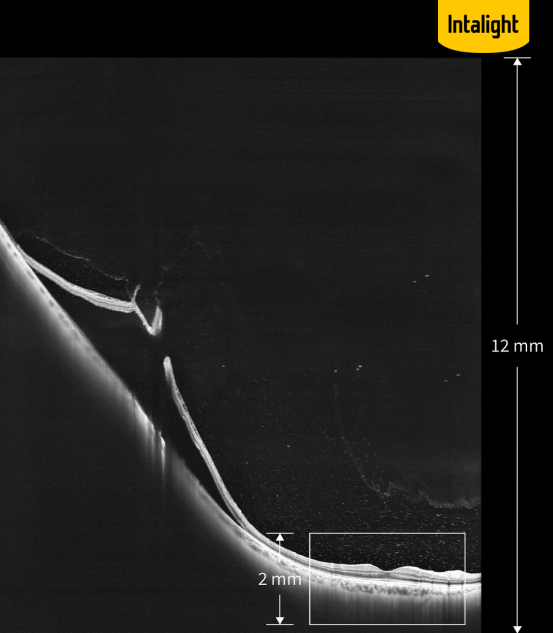

·超深度成像:全新的如意全眼OCT成像眼后节OCT Z大可达12 mm chao . 级 深度成像(组织中),眼前节OCTZ大可达16.2 mm成像深度(空气中),与上一代传统技术相比提升了6倍,对于以往无法完整检查的高度近视、视网膜脱离等病变也能提供完整的病变信息。

如意全眼OCT眼后节12 mm chao . 级深度成像